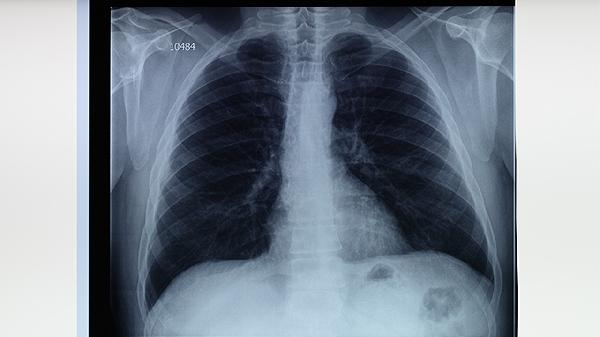

長期吸煙會損害呼吸道纖毛清除功能,降低肺部防御能力,增加結(jié)核分枝桿菌感染概率。吸煙者出現(xiàn)持續(xù)咳嗽、咳痰超過兩周應(yīng)警惕肺結(jié)核可能。建議戒煙并進行胸部X線檢查,確診后需規(guī)范使用抗結(jié)核藥物如鏈霉素注射液等。同時要避免二手煙暴露,保持室內(nèi)空氣流通。